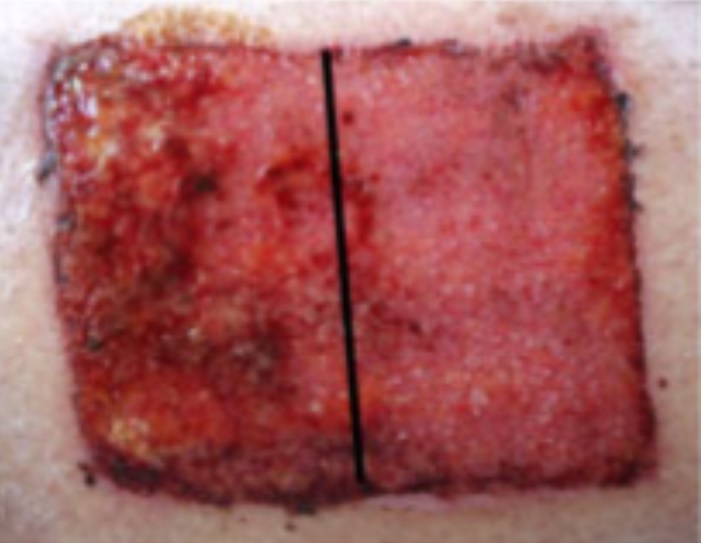

Randomised placebo-controlled human pilot study of cold atmospheric argon plasma on skin graft donor sites

S. Karrer, G. Isbary et al (2013)

University Hospital Regensburg, Germany

Status: Trial completed in 2012 and published

Total number of patients in study: 40